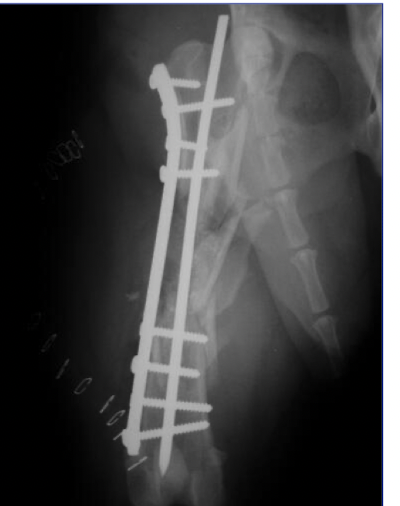

plate rod fixation is — with —

IM pin with bridging plate

the IM pin will help align bone and maintain bone length while increasing resistance to bending

plate/rod fixation will reduce strain on the plate by —. and will increase fatigue life of plate by —

2x

10x

how big of IM pin or plate/rod fixation

A

35-40% of medullary cavity

allow screw placement

avoids excessive rigidity

normograde insertion (top down)

how many screw for plate/rod fixation

4 cortices on each side of fracture at least

IM pin and plate, pin can get in the way and need to use monocortical screws

— is a good fixation technique for comminuted diaphyseal fractures

Plate/rod

IM pin and plate